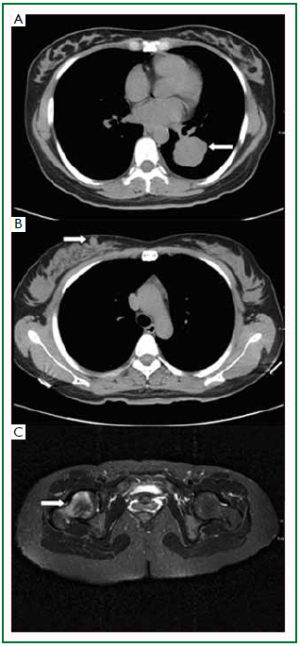

A 49-year-old, non-smoking, peasant woman presented to the general surgery clinic complaining a painless mass in her left breast for 3 months. Physical examination confirmed a round, firm, and non-tender mass located in the lower inner quadrant of her left breast. It was measured 3cm in diameter, mobile and no skin involvement. Axillary and cervical chain lymph nodes were not palpable. A chest computed tomography (CT) scan showed a round-shaped mass (3.2 cm × 3.1 cm) in the apicoposterior segment of her right lung, with a well-defined, lobulated edge and pleural indentation (Figure 1A). No lymphadenectasis of mediastinum was observed. One subcutaneous mass was noted in the lower inner quadrant of the left breast (Figure 1B).

A review of systems did not reveal other symptoms such as dry cough, dyspnea or tachypnea. A left breast lumpectomy was performed and biopsy confirmed a poorly differentiated adenocarcinoma. A lumbar spine magnetic resonance imaging (MRI) showed another metastasis to the 3rd lumbar vertebrae (Figure 1C). The patient refused any further treatment and died 5 months after discharge.

Figure 1. Preoperative radiology of lesion in patient case 1. A: Chest CT image of the apicoposterior segment showed a round, 3.2 cm × 3.1 cm mass in the right lung; B: CT scan also demonstrated a 3 cm-diameter subcutaneous mass in the left breast; C: MRI revealed a metastasis to the 3rd lumbar vertebrae. Arrows indicate the tumor lesion.